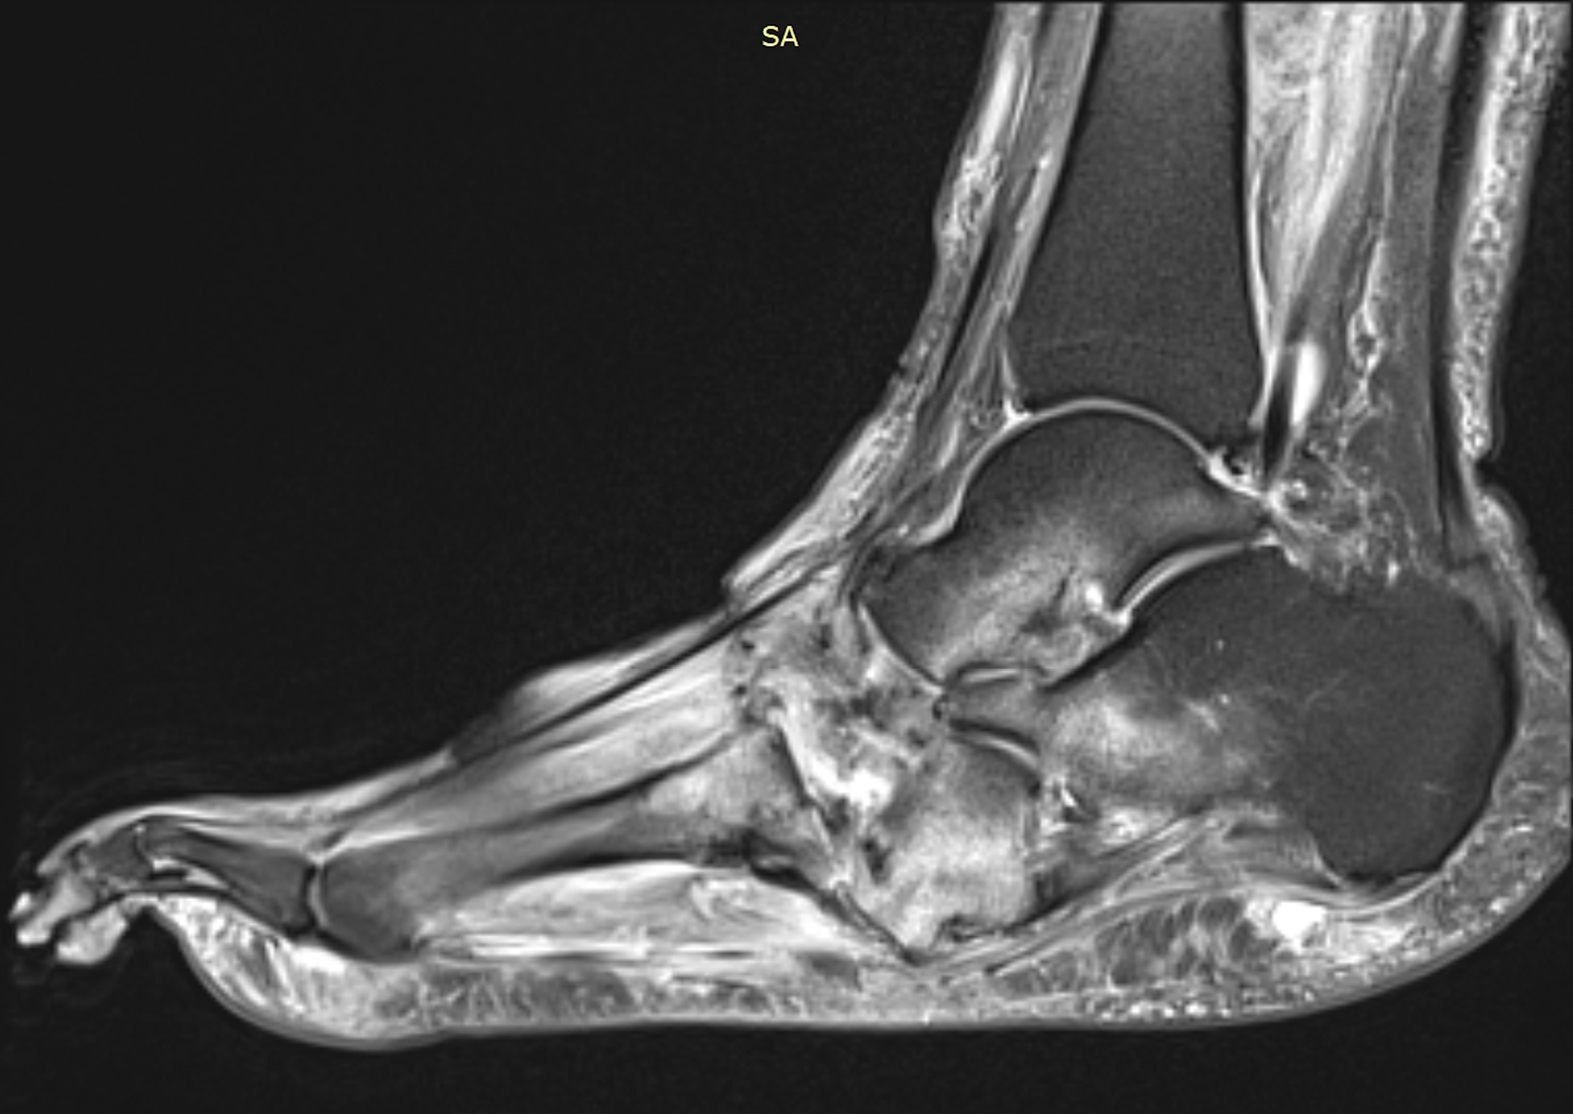

Рис. 8. Исходная МР-томограмма стопы. Режим жироподавления. Сагиттальный срез. Отек костей предплюсны, проксимальной головки II плюсневой кости, кубовидной, таранной, пяточной костей. Деструкция клиновидной кости.

Рис. 9. МР-томограмма стопы от 01.2019. Режим жироподавления. Сагиттальный срез. Отек кубовидной кости уменьшился, отек таранной и пяточной костей не определяется. В остальном – без динамики.